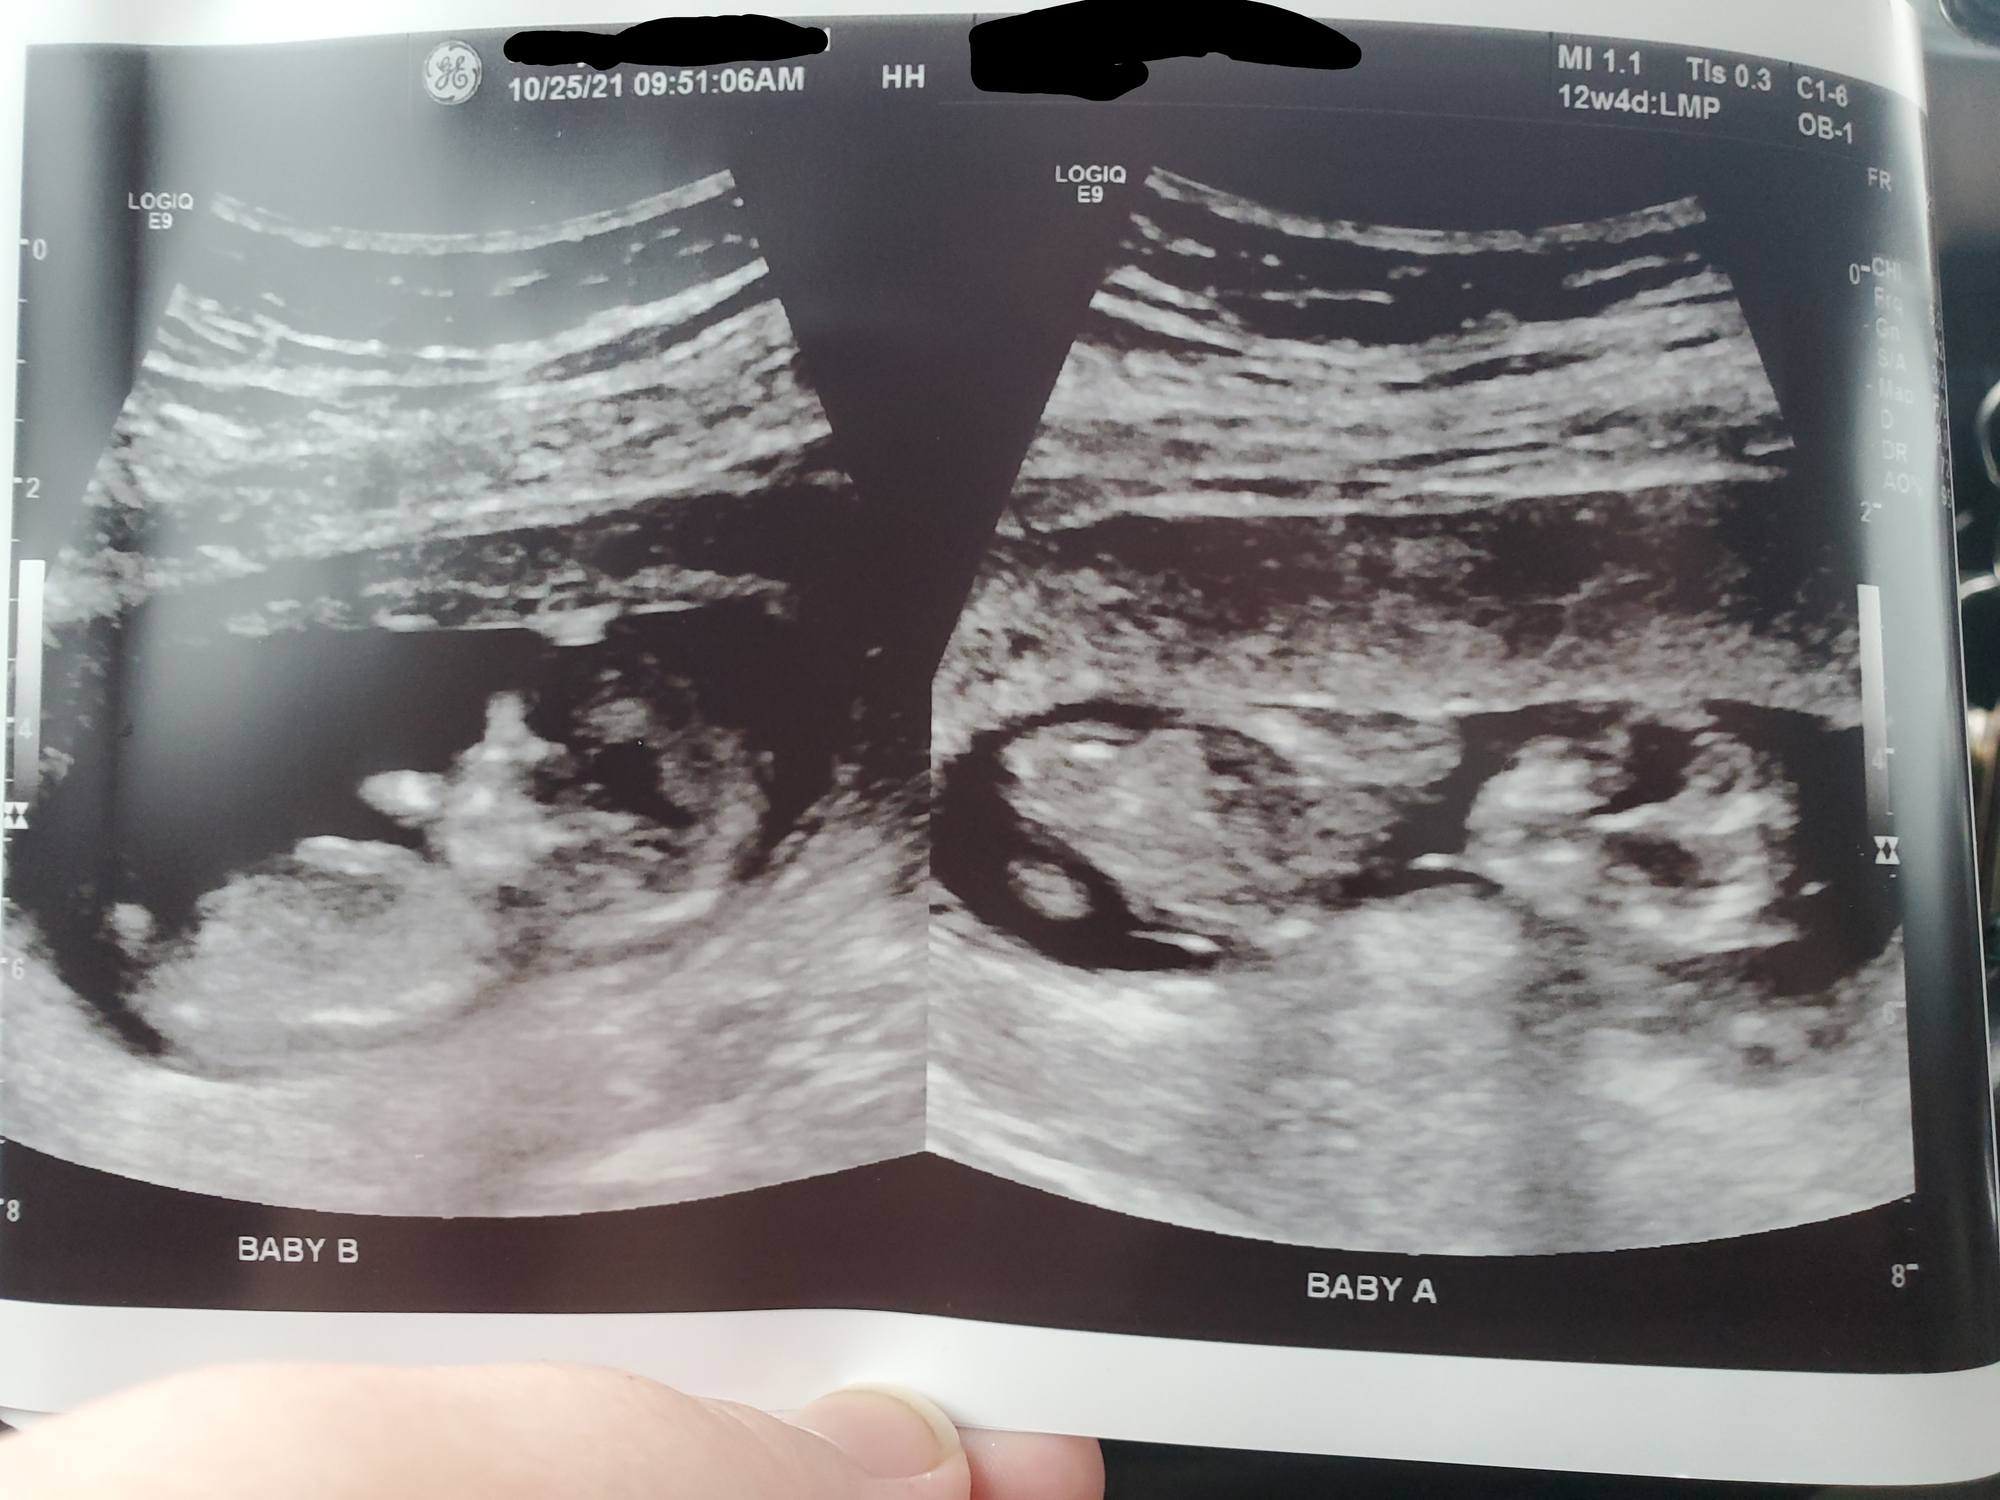

Anatomy scan went well this morning. Still waiting on the doc's report but everything seemed fine? Babies are measuring 14oz & 15oz. Carrying almost 2lbs of baby already.

Married 11.12.11 JB 08.02.13 EC 12.11.15 GE 04.04.19 #4 & #5 due 05.05.22